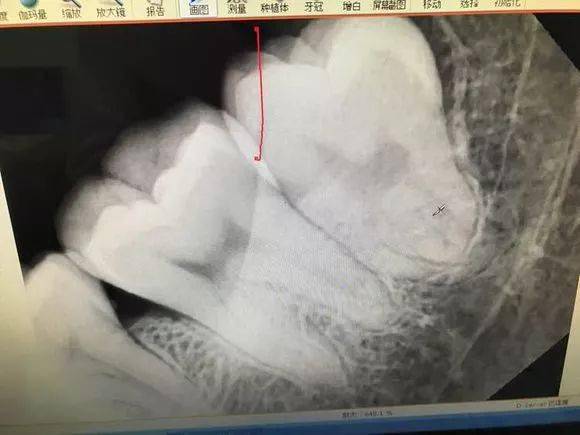

难度三噩梦模式 最后介绍一下,牙根弯曲,骑在下颌管上的智齿...由于下颌管内神经丰富,拔除的时候需要非常小心,而且看长相也知道这种模式的拔牙,非常难也非常贵! 也是先切开牙肉,翻开并露出骨头,切下牙冠后取出,再处理下面的牙根

把牙根分成两半,根据牙根的走向,分别小心地撬出来,这个过程十分考验技术,要谨慎避免损伤到下颌神经... 牙医拔除智齿,需要应对哪些风险 严格地说,拔牙是一个手术,是具有一定风险的

1.2 恰当检查 包括高质量的X线片,它不仅能提供牙齿的清晰图像,牙根的轮廓和解剖以及牙周骨质情况,还能提供牙齿与邻牙和其他结构之间的关系,其中尤其是下颌骨下缘、下颌骨升支以及下牙槽神经束之间的关系